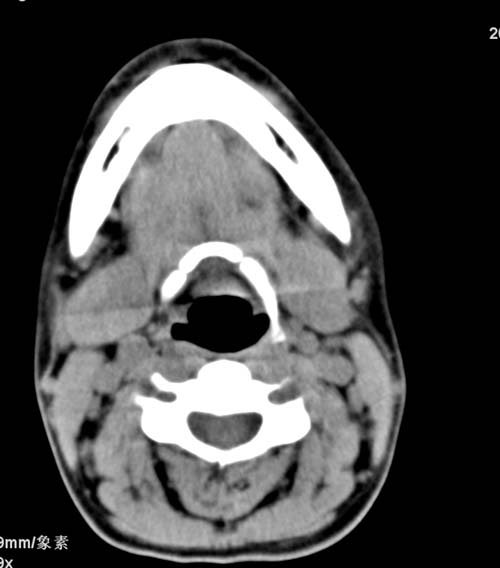

标题: CT22662:女 23 自述双侧颌下腺肿大年余 近来疼痛 左侧明显 [打印本页]

标题: CT22662:女 23 自述双侧颌下腺肿大年余 近来疼痛 左侧明显

见双侧颌下腺略肿大  未见结石及钙化 考虑双侧慢性炎症 ?请指教